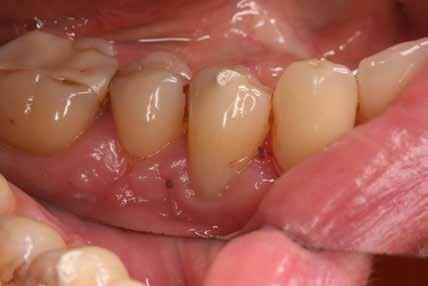

09.40–10.40 Dr. Baktai Zoltán: Helyes Drill & Fill a moláris régióban – tippek, trükkök esetbemutatásokon keresztül

Előadásomban olyan eseteket fogok bemutatni, amelyekkel mindannyian találkozunk a hétköznapjainkban. Átvesszük a nehézségeket, és olyan apró, de nagyon fontos döntéshozatali dilemmákat fogok kihangsúlyozni, amelyek végül hasznos tippként segíthetnek megoldani az ilyen és ehhez hasonló kompozit helyreállításokat. Bízom benne, hogy a kedves kollégák olyan praktikai tanácsokkal fognak gazdagodni, amelyeket akár a legközelebbi munkanapjukon hasznosítani is tudnak.

Gyökérkezelendő posterior fogak esetén gyakran találkozunk mély, szubgingivális szuvassággal az approximális területen, melynek szanálása elengedhetetlen előfeltétele a fog endodonciai kezelésének. Az így kialakuló, már kitisztított üreg restaurálása gyakran nehezen kezelhető szituációt teremt a klinikai gyakorlatban. Ezt sokan „endodonciai csonkfelépítésként” kezelik, mely magában rejthet egy ideiglenes jelleget is, holott ez teljesen téves irány. A jelenlegi modern angol nómenklatúra, azaz a „Deep Margin Elevation (DME)” sokkal jobban tükrözi a beavatkozás célját és nehézségét is. Ugyanis a DME a legnehezebb körülmények között elvégzendő adhezív beavatkozásnak minősül. Emellett a teljes, végleges restaurátum sikerességét meghatározza, és kulcsfontosságú a fog megtarthatóságának eldöntési folyamatában: „ha nem tudjuk megfelelően elvégezni, ugyan hogyan akarjuk most vagy a későbbiekben kezelni és megtartani az érintett fogat?” Előadásomban szeretnék bemutatni egy a jelenlegi szakirodalmon alapuló modern, könnyen kivitelezhető protokollt és néhány trükköt, amelyek megkönnyíthetik és kiszámíthatóbbá tehetik ezeknek az erősen destruált fogaknak a helyreállítását.